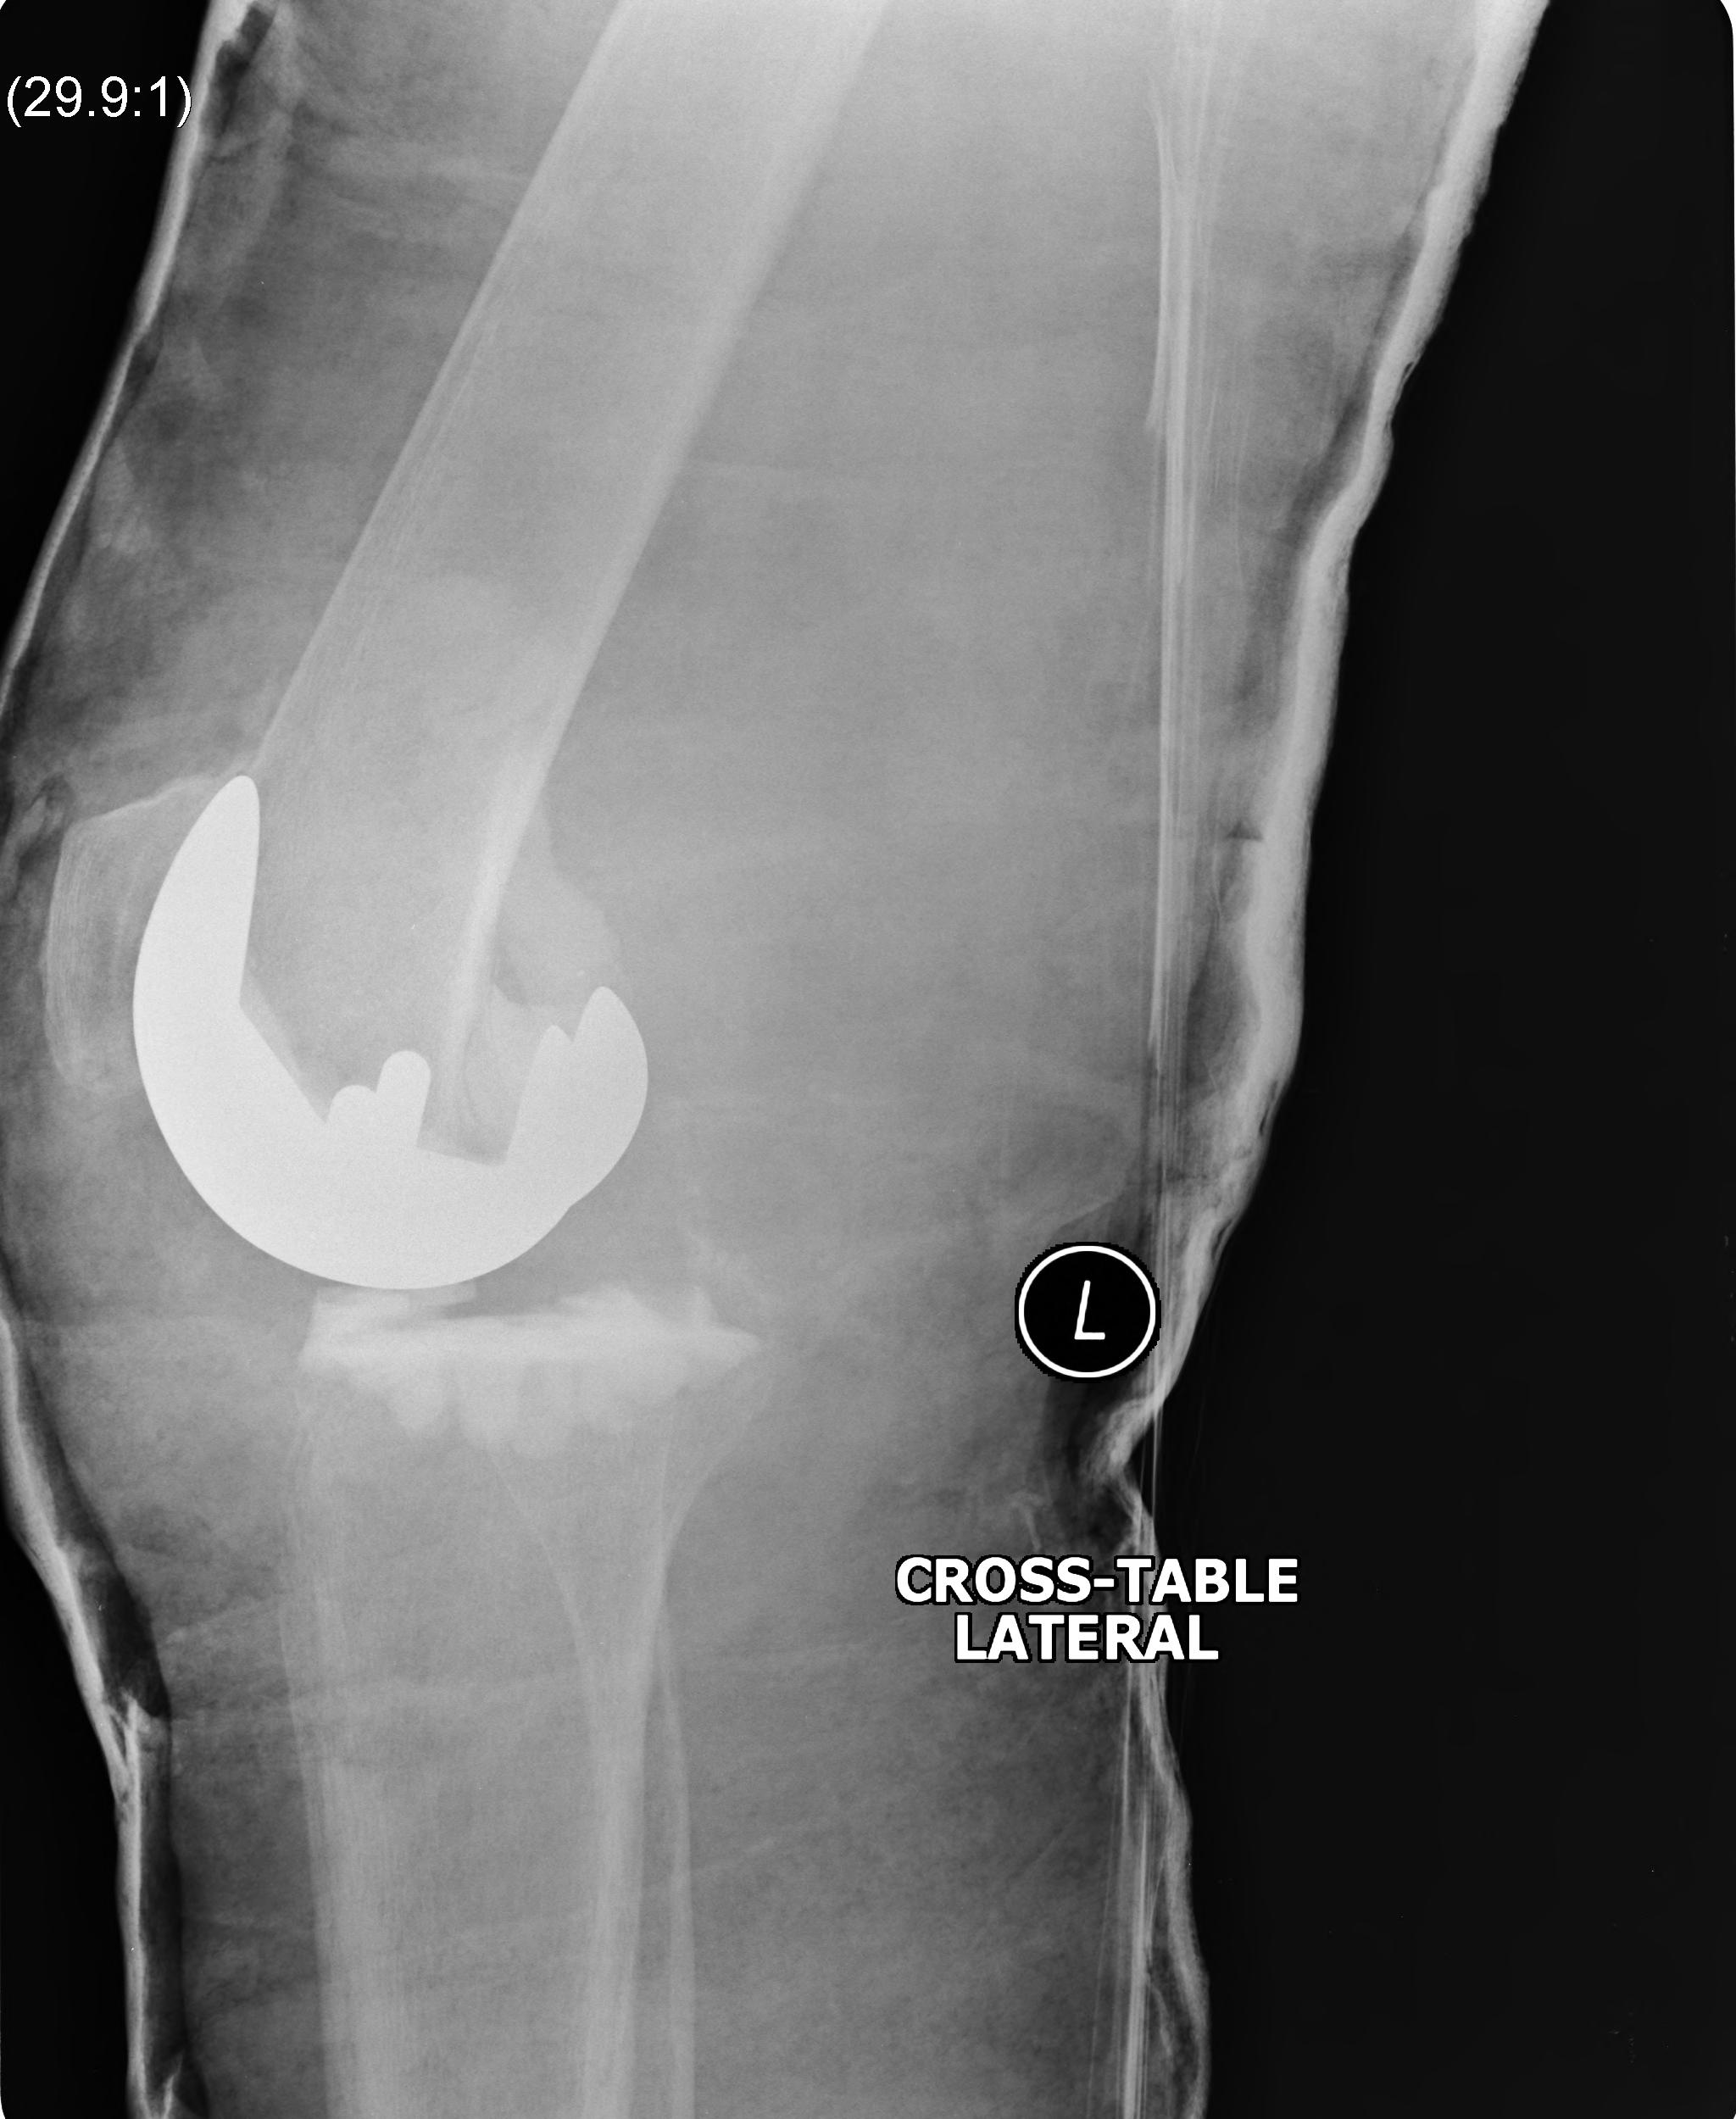

1. Loosening

2. Infection

3. Instability

4. Periprosthetic fracture